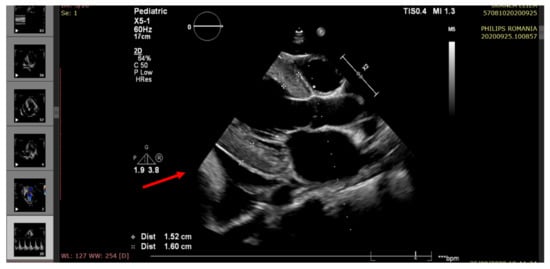

| Right ventricular ejection fraction RV EF (%) | >60 | 55 | 50 | 55 | 45 |

| Left ventricular ejection fraction LV EF (%) | >60 | 60 | 35 | 45 | 25 |

| Mitral annular plane systolic excursion (MAPSE) (mm) (M-mode) | 16.4 ± 2.4 | 15 | 9.2 | 12.2 | 8.3 |

| Pericardial fluid (edge) | <5 mm | Small (6 mm) | Raised (20 mm) | Moderate (14 mm) | Large (22 mm) |

| Pulmonary hypertension (echocardiographic criteria) | Normal | Mild | Moderate | Mild | Moderate/severe |